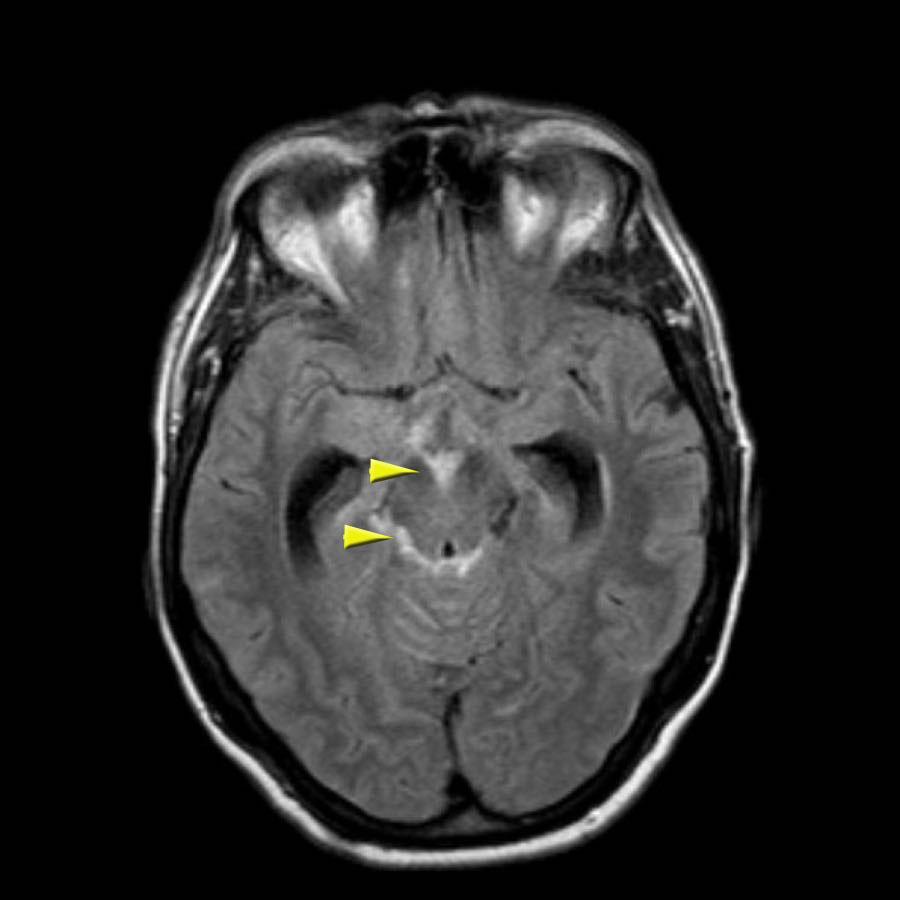

Lưu ý ổ xuất huyết ở cầu não (mũi tên vàng).

Có hình ảnh nhiễm sắt bề mặt ở vùng chẩm trái.

Chuỗi xung DWI cho thấy ổ nhồi máu ở thùy chẩm trái và thùy trán phải (kèm theo một số xảo ảnh).